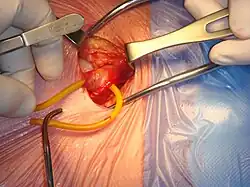

Open surgical repair of a right inguinal hernia

All techniques involve an approximate 10-cm incision in the groin. Once exposed, the hernia sac is returned to the abdominal cavity or excised and the abdominal wall is very often reinforced with mesh.[11] There are many techniques that do not utilize mesh and have their own situations where they are preferable.[25][17]